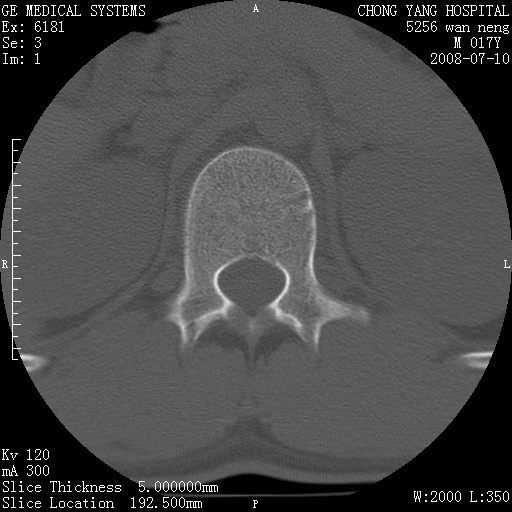

腰3、4椎弓崩裂

腰3、4椎弓不连

支持:腰3、4椎弓峡部崩裂。

腰3、4椎弓峡部不连

支持:腰3、4椎弓峡部崩解。

腰3、4,如受过外伤则为陈旧骨折,否则为骨质不连

图片漂亮,目前也只能看到腰3、4骨质不连

腰3、4椎弓峡部裂。

腰3、4椎弓峡部裂。支持

重建图像见多个椎弓峡部不连(不足为据),平扫未见异常。

支持腰3、4椎弓峡部崩裂。